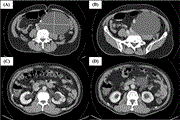

Hypercalcemia an exceptional complication in upper urinary tract urothelial carcinoma

Issam Jandou and others

Journal of Surgical Case Reports, Volume 2021, Issue 2, February 2021, rjaa574, https://doi.org/10.1093/jscr/rjaa574